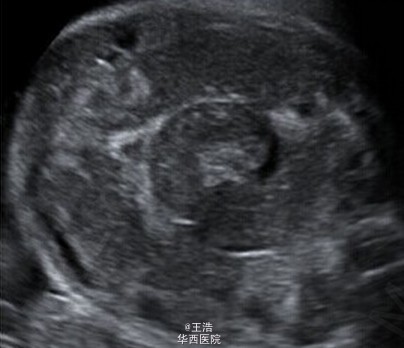

一名 35 岁初产妇,孕龄到达 30 周时出现了宫缩征象,但没有显示胎儿窘迫。超声显示胎儿发育,多普勒指数,羊水均正常。发现强回声的肠管轻度扩张,但不伴有形态学异常。病原体(TORCH)筛查阴性。第二天检查发现肠扩张伴有高回声点推断发生了进展并出现腹水,因此怀疑肠穿孔和胎粪性腹膜炎。 于是对产妇进行了紧急剖腹产。剖出一名男婴,重 2620g,在第 5 分钟及第 10 分钟 Apgar 得分都是 9 分。新生儿呼吸不稳定,腹部重度膨胀水肿呈铁青色,腹膜炎。对新生儿进行了紧急剖腹手术。术中发现证实了接生前的的诊断。切除了 50cm 坏死的回肠,且必要的实施了肠造口术。Takacs ZF, Meier CM, Solomayer EF, Gortner L, Meyberg-Solomayer G. 2014. Prenatal diagnosis and management of an intestinal volvulus with meconium ileus and peritonitis. Arch Gynecol Obstet. 290(2): 385-7.